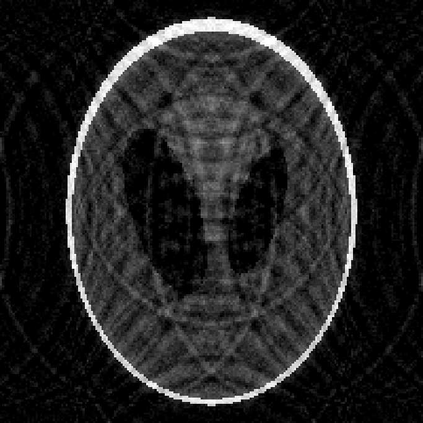

Image reconstruction based on indirect, noisy, or incomplete data remains an important yet challenging task. While methods such as compressive sensing have demonstrated high-resolution image recovery in various settings, there remain issues of robustness due to parameter tuning. Moreover, since the recovery is limited to a point estimate, it is impossible to quantify the uncertainty, which is often desirable. Due to these inherent limitations, a sparse Bayesian learning approach is sometimes adopted to recover a posterior distribution of the unknown. Sparse Bayesian learning assumes that some linear transformation of the unknown is sparse. However, most of the methods developed are tailored to specific problems, with particular forward models and priors. Here, we present a generalized approach to sparse Bayesian learning. It has the advantage that it can be used for various types of data acquisitions and prior information. Some preliminary results on image reconstruction/recovery indicate its potential use for denoising, deblurring, and magnetic resonance imaging.